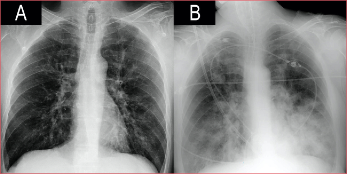

Varón de 53 años, con diabetes tipo 2 en tratamiento con insulina y mal controlada (HbA1c 11%). Acudió al Departamento de Urgencia por un cuadro catarral de cuatro días de evolución. A su llegada tenía insuficiencia respiratoria e hipotensión, la radiografía no mostraba infiltrados parenquimatosos (Figura 1). La reacción en cadena de la polimerasa fue positiva para el virus influenza A (subtipo H1N1 variante 2009), por lo que se inició el tratamiento con oseltamivir junto con ceftriaxona y levofloxacina. El antígeno urinario para Streptococcus pneumoniae y Legionella pneumophila tipo 1 fue negativo. Tras 24 h, el estado clínico empeoró y se decidió el ingreso en la Unidad de Cuidados Intensivos. Los análisis de laboratorio revelaron leucocitosis y marcadores inflamatorios elevados. A pesar del soporte respiratorio con oxigenoterapia de alto flujo, el paciente no mejoró y requirió intubación orotraqueal y ventilación mecánica invasiva. En la radiografía posintubación, apareció una condensación incipiente en el lóbulo inferior izquierdo, por lo que se sustituyó ceftriaxona por meropenem. Las siguientes 48 h estuvieron marcadas por un empeoramiento progresivo: insuficiencia respiratoria a pesar de la ventilación protectora, shock con pobre respuesta a fármacos vasoactivos e inotrópicos, coagulopatía e insuficiencia renal aguda, con anuria. Se inició hemodiafiltración venovenosa continua. A las 72 h del ingreso en la Unidad de Cuidados Intensivos, continuó la progresión clínico-radiológica con evidencia de infiltrados bilaterales algodonosos (Figura 1) y aumento de la necesidad de FiO2.

Figura

1. Evolución radiográfica en las primeras 72 horas.

Es importante destacar que, dentro de las alteraciones en los estudios por imágenes, se aceptan no solo los hallazgos típicos en la TC (signo del halo o nódulos pulmonares múltiples rodeados de áreas de vidrio deslustrado),11 sino también las alteraciones visibles en la radiografía portátil. Con esto se pretende incluir dentro del algoritmo a pacientes inestables que no puedan ser trasladados a la sala de radiodiagnóstico, como ocurrió en nuestro caso, donde la rápida progresión radiológica paralela a la mala evolución clínica fueron criterios suficientes para iniciar la terapia antimicótica sin necesidad de una TC.